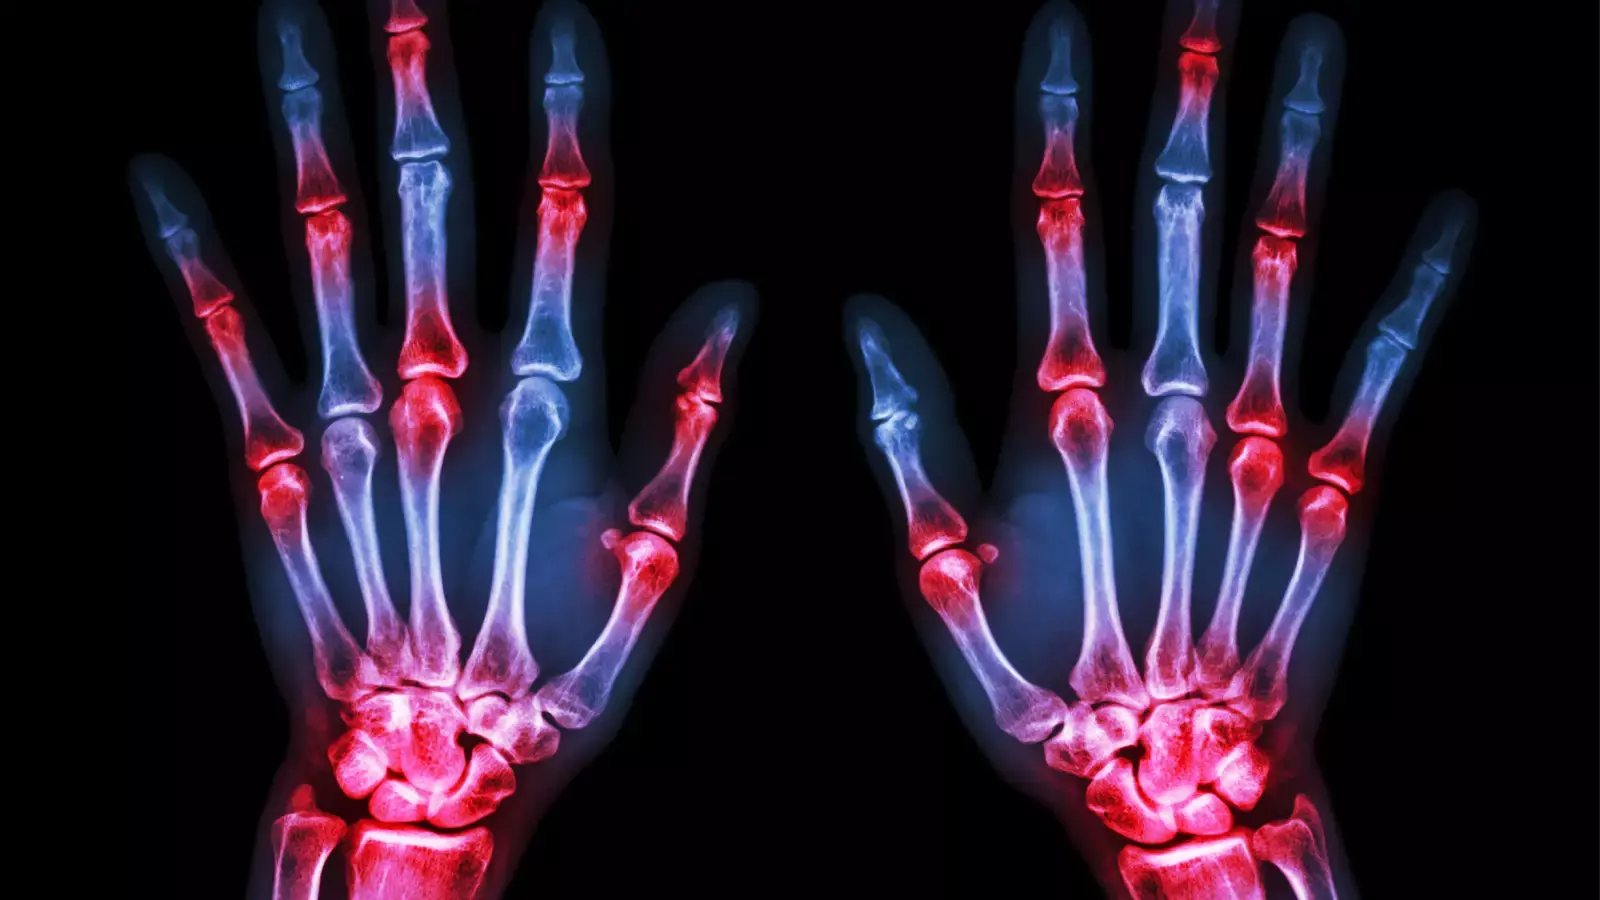

مرض التهاب المفاصل الروماتويدي هو أحد أمراض المناعة الذاتية التي يهاجم فيها الجهاز المناعي أنسجة الجسم نتيجة لوجود خلل به ، حيث يقوم الجهاز المناعي بمهاجمة المفاصل خصوصًا في اليدين والرسغين والركبتين مسببا التورم المؤلم بها مما يؤدي في النهاية إلى تآكلها وإلى حدوث تشوه المفاصل و العظام ، و قد يؤثر في الأنسجة الأخرى مسببا مشكلات في بعض أعضاء الجسم، مثل: الرئتين، والقلب، والعينين.

في البداية يصيب التهاب المفاصل الروماتويدي المفاصل الصغيرة اولا مثل أصابع اليدين والقدمين ثم يتطور الأمر مع مرور الوقت إلى اصابة المفاصل الكبيرة مثل الرسغ والركبة والكاحل والمرفق والفخذ والكتف ، و يمر المريض بفترات تكون فيها الأعراض شديدة و اوقات اخرى تخف فيها حدة الأعراض.